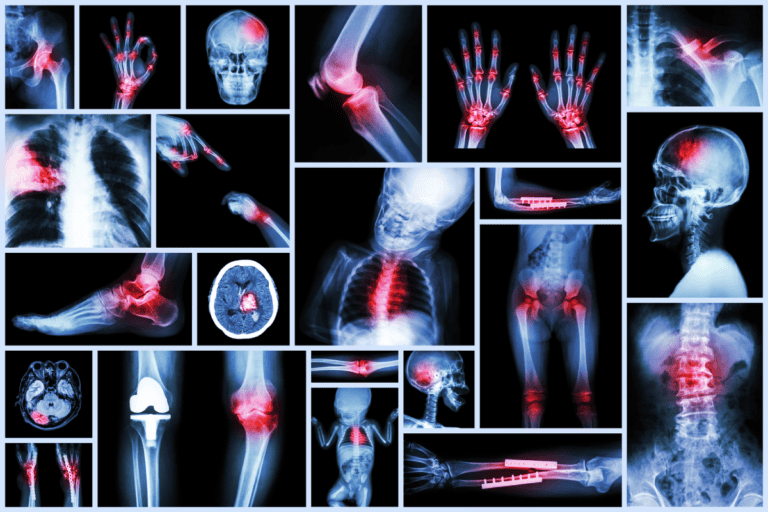

La influencia del deporte en la salud humana es más que obvia.

Con cada entrenamiento que haces, te sientes mejor, tu mente se despeja y tu cuerpo te lo agradece mandando todo tipo de estímulos químicos dentro del cuerpo.

En esta categoría de la página web se hablará de todo lo relacionado con el bienestar deportivo.

Desde el envejecimiento, diabetes, cáncer, hiperlordosis, colesterol, autofagia y un largo etc. Todo ello ligado al ejercicio y a los efectos que tiene éste sobre el cuerpo.